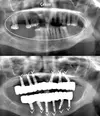

علاج الزرع